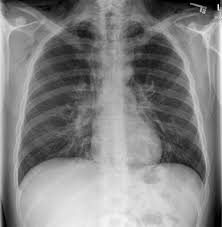

Pneumothorax / Case Report Covid 19 Associated Bilateral Spontaneous Pneumothorax A Literature Review In The American Journal Of Tropical Medicine And Hygiene Volume 103 Issue 3 2020 / Tension pneumothorax most commonly occurs in people with penetrating chest injuries.. This may be caused by physical trauma to the lung, such as a wound. Pneumothorax nursing interventions, treatment, pathophysiology nclex review for the different types of pneumothorax: There are several variations of pneumothorax. Pneumothorax is the medical term for a collapsed lung, a condition in which air or gas is trapped in the space surrounding the lungs causing the lungs to collapse. Also known as pneumothorax, collapsed lung is a rare condition that may cause chest pain and make it hard to breathe.

This is termed spontaneous pneumothorax. Pneumothoraces can be even further classified as simple, tension, or open. Pneumothorax nursing interventions, treatment, pathophysiology nclex review for the different types of pneumothorax: Pneumothorax, also called a collapsed lung, is when air gets between one of your lungs and the wall of your chest. It is reasonably common and has many different causes.

Scielo Brasil Pneumothorax As A Late Complication Of Covid 19 Pneumothorax As A Late Complication Of Covid 19 from minio.scielo.br In tension pneumothorax, patients are distressed with rapid laboured respirations, cyanosis, profuse diaphoresis, and tachycardia. The definition of a pneumothorax is an accumulation of air outside the lungs, but inside the chest wall. Tension pneumothorax most commonly occurs in people with penetrating chest injuries. In a healthy body, the lungs are touching the walls of the chest. Patients with a pneumothorax typically report dyspnoea and chest pain. A pneumothorax occurs when air leaks into the space between the lung and chest wall (called the pleural space). A small pneumothorax may cause few or no symptoms. Pneumothorax occurs when air enters the space around your lungs (the pleural space).

Other signals that the problem may be a collapsed lung are: Normally, the outer surface of the lung sits next to the inner surface of the chest wall. The lung and the chest wall are covered by thin membranes called pleura. It occurs when air accumulates between the parietal and visceral pleura inside the chest. Pneumothoraces can be even further classified as simple, tension, or open. A pneumothorax is an abnormal collection of air in the pleural space between the lung and the chest wall. Pneumothorax is defined as the presence of air or gas in the pleural cavity (ie, the potential space between the visceral and parietal pleura of the lung), which can impair oxygenation and/or. A pneumothorax occurs when air leaks into the space between your lung and chest wall. The pressure causes the lung to give way, at least partly. Pneumothorax is classified as spontaneous or traumatic. Hemothorax occurs when there is blood in that. This air pushes on the lung, which makes it collapse. The air accumulation can apply pressure on the lung and make it collapse.

In a healthy body, the lungs are touching the walls of the chest. A pneumothorax is a collection of air outside the lung but within the pleural cavity. It is reasonably common and has many different causes. Open pneumothorax vs closed pneumothorax. Pneumothorax, also called a collapsed lung, is when air gets between one of your lungs and the wall of your chest.

Patients with a pneumothorax typically report dyspnoea and chest pain. Pneumothoraces can be even further classified as simple, tension, or open. Pneumothorax is defined as the presence of air or gas in the pleural cavity (ie, the potential space between the visceral and parietal pleura of the lung), which can impair oxygenation and/or. In a healthy body, the lungs are touching the walls of the chest. The definition of a pneumothorax is an accumulation of air outside the lungs, but inside the chest wall. It is reasonably common and has many different causes. A pneumothorax is a collection of air outside the lung but within the pleural cavity. A pneumothorax can be a complete lung collapse or a collapse of only a portion of the lung. A pneumothorax occurs when air leaks into the space between the lung and chest wall (called the pleural space). This air pushes on the lung, which makes it collapse. Also known as pneumothorax, collapsed lung is a rare condition that may cause chest pain and make it hard to breathe. A large pneumothorax can squash the lung and cause it to collapse. This is termed spontaneous pneumothorax.